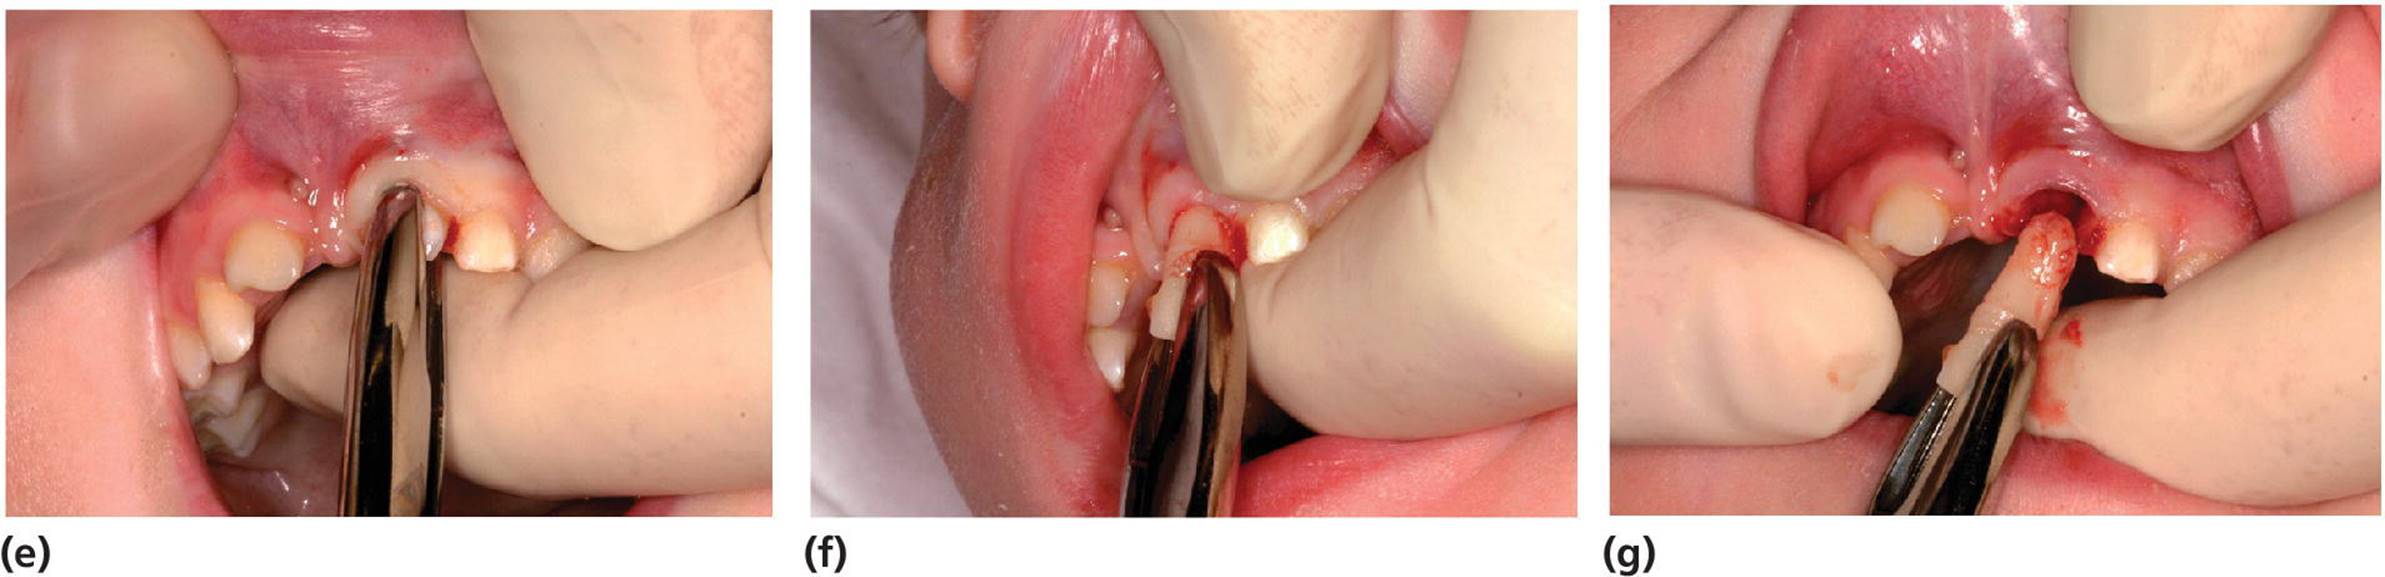

The indications, contraindications and techniques for extraction of teeth in children and adolescents are somewhat different from those in adults. In the primary dentition more radical treatment may, for many reasons, be applied. Generally, necrotic teeth, ankylosed primary teeth without permanent successors, seriously decayed teeth, especially with advanced root resorption, and primary incisors exposed to severe traumatic injuries should be extracted. The forceps used for extraction of primary teeth are specially designed for the anatomical form and size of these teeth. The risk of root fractures during the extraction procedure is somewhat higher for primary molars than for permanent teeth due to the more slender and curved roots. Therefore, careful loosening of the tooth with a straight elevator is recommended before the forceps are applied. It is important to have a firm grip of the jaw in order to control the movement of the forceps more easily and to apply the working branches of the forceps steadily around the crown and neck of the tooth deep in the gingival pocket. The primary molars are extracted by slightly pressing the tooth down in the socket and slowly moving the tooth in a bucco‐lingual direction to enlarge the socket before the tooth is lifted out. Incisors are extracted by a slight rotation of the tooth (Figure 15.24).

Figure 15.24 Extraction of primary teeth: (a, b) molars in upper jaw and (c, d) lower jaw – loosen the tooth carefully with an elevator, place the forceps around the tooth and apply apical pressure and buccal–lingual movements before the tooth is lifted out. (e–g) Incisors are extracted by slight apical pressure and rotary movement.